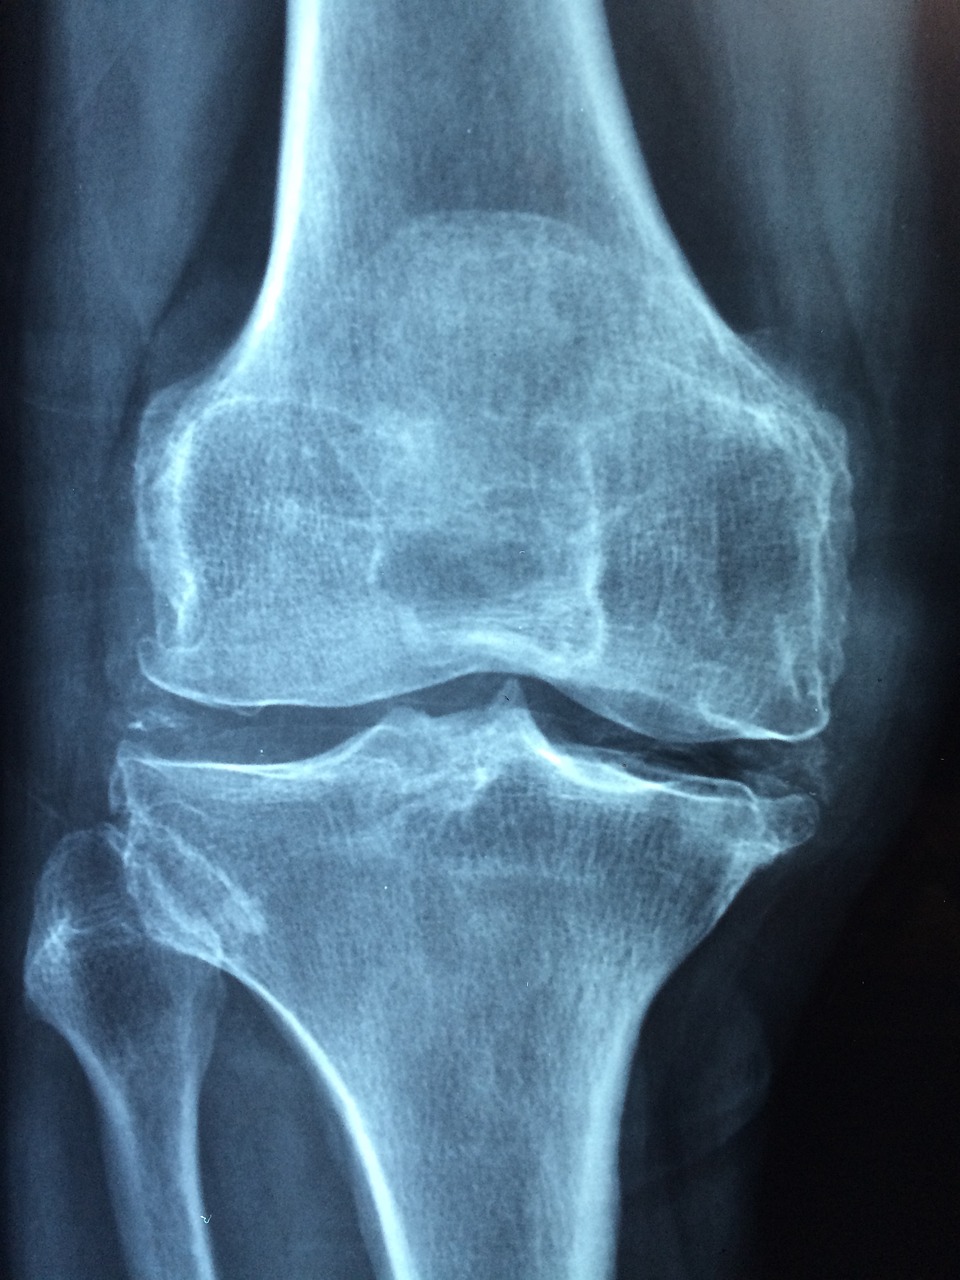

병원에서는 혈액검사, 엑스레이, 관절액 검사 등을 통해 감염 여부를 정확히 판단합니다.